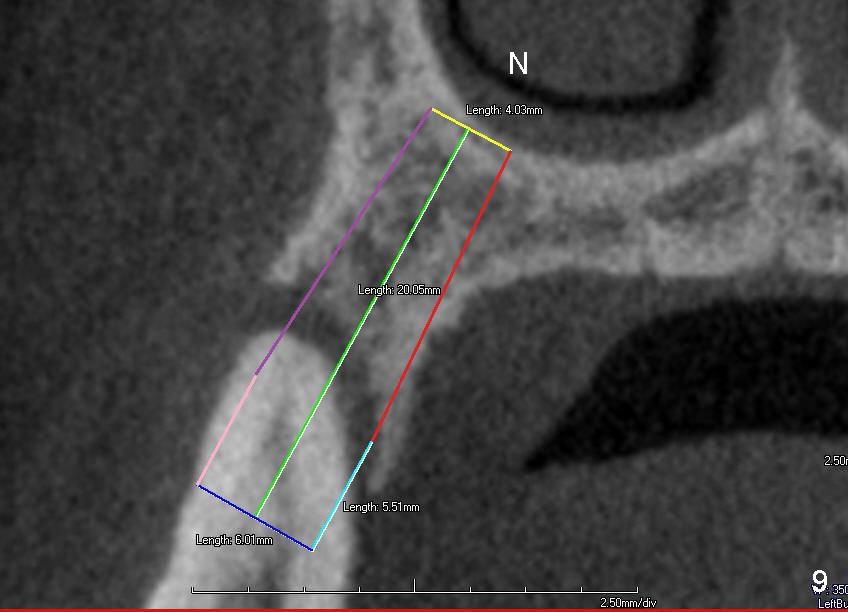

Fig.5 is an illustration showing the socket after extraction. The osteotomy is intentionally placed distally (Fig.6 arrow: pilot drill). In case the patient agrees to have ortho treatment, there will be space to correct the upper midline (7). If not, a molar crown will be fabricated. By the time a 4.5x20 mm tap is inserted (Fig.7 T), the mesial gap is visible (*). When a 6x20 mm implant is placed (Fig.8 I), bone graft is placed buccally (Fig.2, as planned) and mesially (Fig.8 red circles, as compared to Fig.1). The implant has to be as large and long as 6x20 mm to get primary stability (insertion torque 50/60 Ncm). The apex of the implant is close to the sinus floor (Fig.8 ^) or in fact the nasal floor (Fig.9 N). There appears bone growth in the mesial gap 3 months postop (Fig.10 *). There is no bone loss 2.5 years post cementation (Fig.11).

CT taken 4 years 9 months post cementation shows that the coronal portion of the buccal plate regenerates (Fig.12 between arrowheads, as compared to Fig.2,9). The density is ~1,000 Hounsfield Units, as compared to ~2,000 HU of the apical portion (Fig.13).